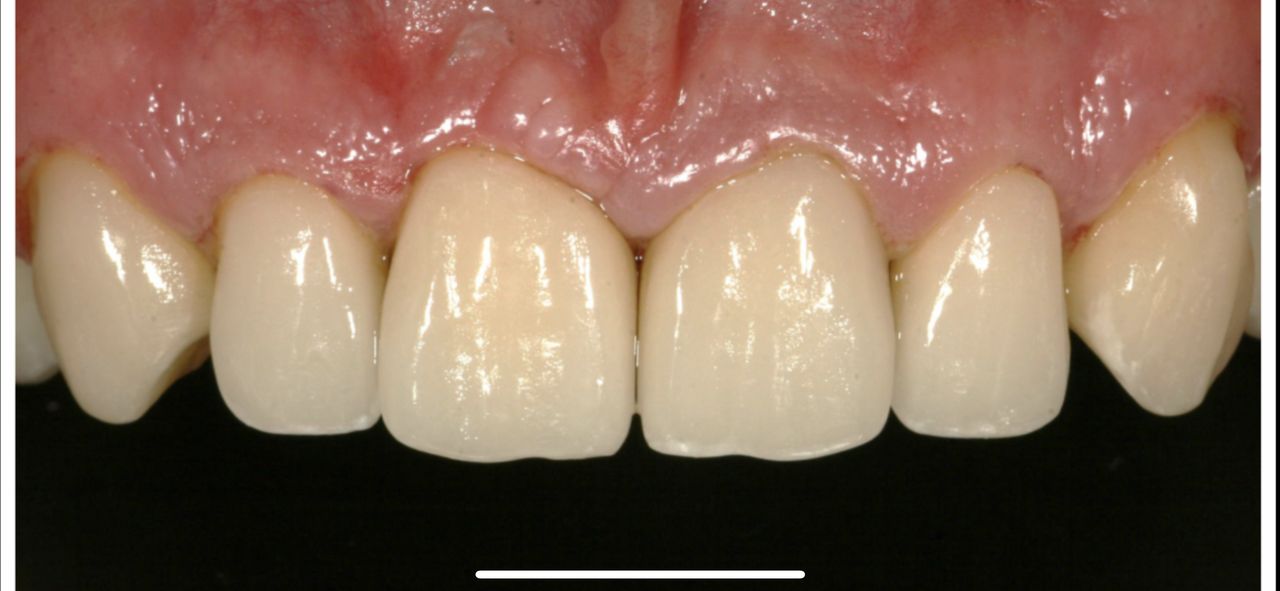

Zdjęcia i filmy

Z pełnym przekonaniem polecam leczenie protetyczne w tym gabinecie. Wykonane korony porcelanowo-cyrkonowe spełniły moje oczekiwania zarówno pod względem estetycznym, jak i funkcjonalnym. Efekt końcowy jest bardzo naturalny, korony są idealnie dopasowane i komfortowe w codziennym użytkowaniu. Cały proces leczenia przebiegał sprawnie, z dokładnym omówieniem planu oraz poszczególnych etapów. Lekarz wykazał się dużą wiedzą, precyzją i dbałością o detale, co w protetyce ma kluczowe znaczenie. Dodatkowo czułem się zaopiekowany i spokojny, co zdecydowanie podnosi komfort leczenia.

• Duo-Dent korony cyrkonowe  •

Pan dok.Polakowski to profesjonalista, tam gdzie nikt nie chciał zająć się moimi zębami

P.dok wyczarowal piękny uśmiech.

• Duo-Dent odbudowa zębów  •